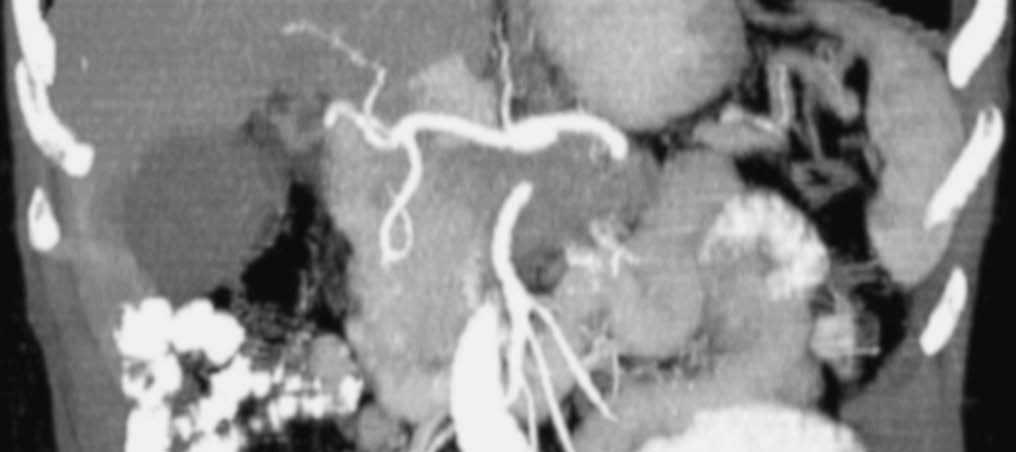

El estudio dinámico volumétrico tridimensional con saturación grasa permite una precisa visualización de las estructuras vasculares arteriales y venosas peripancreáticas50,51, lo que posibilita la evaluación de la extensión vascular local (fig. 11). Hochwald et al52 revisan retrospectivamente los estudios de RM y de colangiopancreatografía por RM (CPRM) de 21 pacientes con sospecha de cáncer de páncreas para determinar su resecabilidad. La técnica detectó todas las lesiones y mostró un rendimiento diagnóstico para diferenciar entre lesiones pancreáticas malignas y benignas del 81%, y del 43% para predecir la afectación ganglionar. En cuanto a la predicción de la resecabilidad tumoral, los autores describen una sensibilidad de la técnica del 100%, especificidad del 83%, valor predictivo positivo del 94% y negativo del 100%. La precisión diagnóstica de la RM, incluyendo la CPRM fue del 95%. Los buenos resultados que presentan estos autores muy probablemente se deben a que evalúan la rentabilidad de la RM en 21 pacientes con masa pancreática, aunque sólo 16 de ellos tenían un adenocarcinoma ductal pancreático (10 fueron resecados, mientras que los 6 restantes fueron irresecables). Los datos se han calculado sobre 15 tumores resecables sobre los 21 que constituyen la serie.

López Hänninen et al53, utilizando RM dinámica y CPRM, definen un valor predictivo positivo y negativo para neoplasia irresecable pancreática del 90 y 83% respectivamente, una sensibilidad y especificidad del 69 y 95% y un rendimiento global del 85%. Fischer et al54 presentan un valor predictivo positivo de la RM del 87% para la resecabilidad tumoral local cuando seleccionan sólo los tumores sólidos de su serie, que fueron 29 casos. Los autores definen esta técnica como la de mayor coste-eficacia y la proponen como la única a realizar en el diagnóstico de extensión del cáncer (fig. 12) de páncreas basándose en la política de «todo en uno»: toda la información requerida obtenida en una sola técnica diagnóstica.